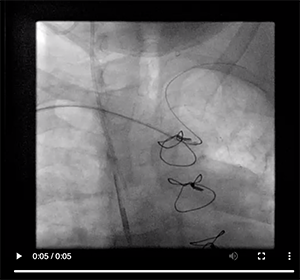

Because the aortic arch was mildly calcified and only mildly tortuous, we were able to negotiate the left subclavian artery with relative ease using a 0.035-inch angled Glidewire Advantage guidewire (Figure 1). Because the patient developed spasm, we chose not to exchange to another catheter and used the JR 4 catheter for the native right coronary artery (Figure 2) and all the grafts, including the LIMA. There was clear diffuse disease progression in the native LAD artery. We discussed intensifying medical therapy and more aggressive dialysis to stabilize her LV function, but we decided against it due to changes in the electrocardiogram and spasm. Video 1 and Video 2 reveal the anatomy defined during catheterization. Video 3, Video 4, and Video 5 illustrate how we negotiated the left subclavian artery and the subselective LIMA angiogram.